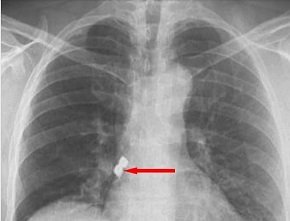

Afyonkarahisar’ın Emirdağ ilçesinde, bir kişinin diş tedavisi sırasında soluk borusuna kaçan iki implant başarıyla çıkarıldı.

Belçika’da yaşayan 56 yaşındaki Emirdağlı gurbetçi Demet Kaplan, geldiği Emirdağ ilçesinde diş tedavisi için bir kliniğe gitti. Operasyon sırasında birbirine yapışık olan 2 implant hastanın dişinden düştü.

Kaplan, yutkununca implantlar soluk borusuna kaçarak burayı tıkadı. Nefes almakta zorlanan Kaplan, Emirdağ Devlet Hastanesinde yapılan ilk müdahalenin ardından Afyonkarahisar’da başka bir hastaneye sevk edildi.

Kaplan’ın akciğer girişinden implantlar başarıyla çıkarıldı.